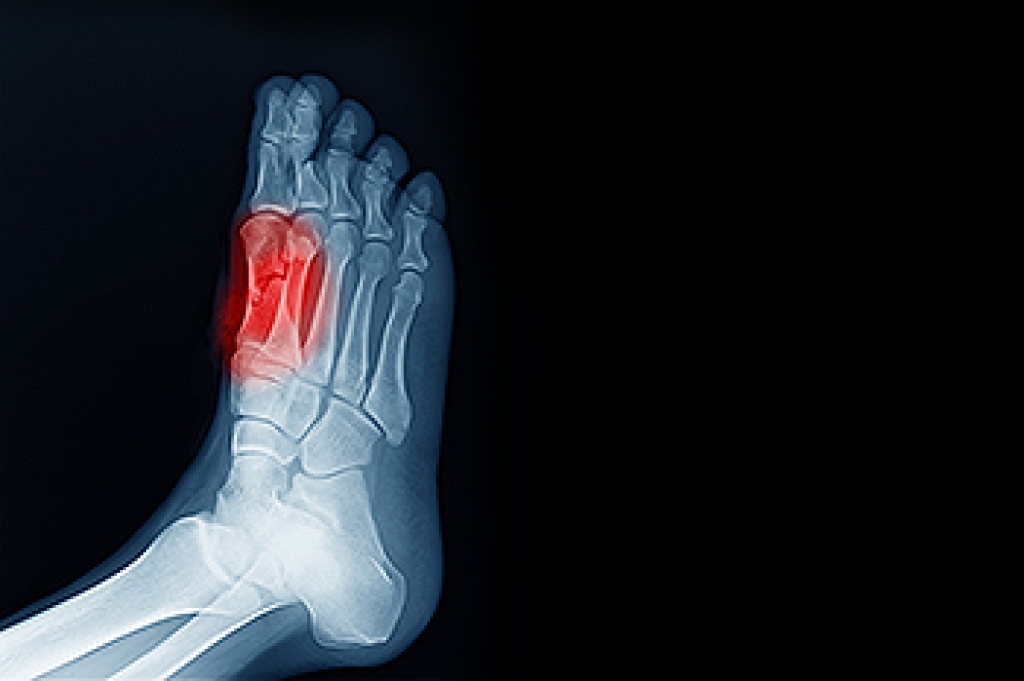

Swollen feet can also be caused by bone and tendon conditions, including fractures, arthritis, and tendinitis. Additionally, there may be skin and toenail conditions and an infection may cause the feet to swell. Patients who take medicine to treat high blood pressure may be prone to getting swollen feet.

Sesamoiditis is a condition of the foot that affects the ball of the foot. It is more common in younger people than it is in older people. It can also occur with people who have begun a new exercise program, since their bodies are adjusting to the new physical regimen. Pain may also be caused by the inflammation of tendons surrounding the bones. It is important to seek treatment in its early stages because if you ignore the pain, this condition can lead to more serious problems such as severe irritation and bone fractures.